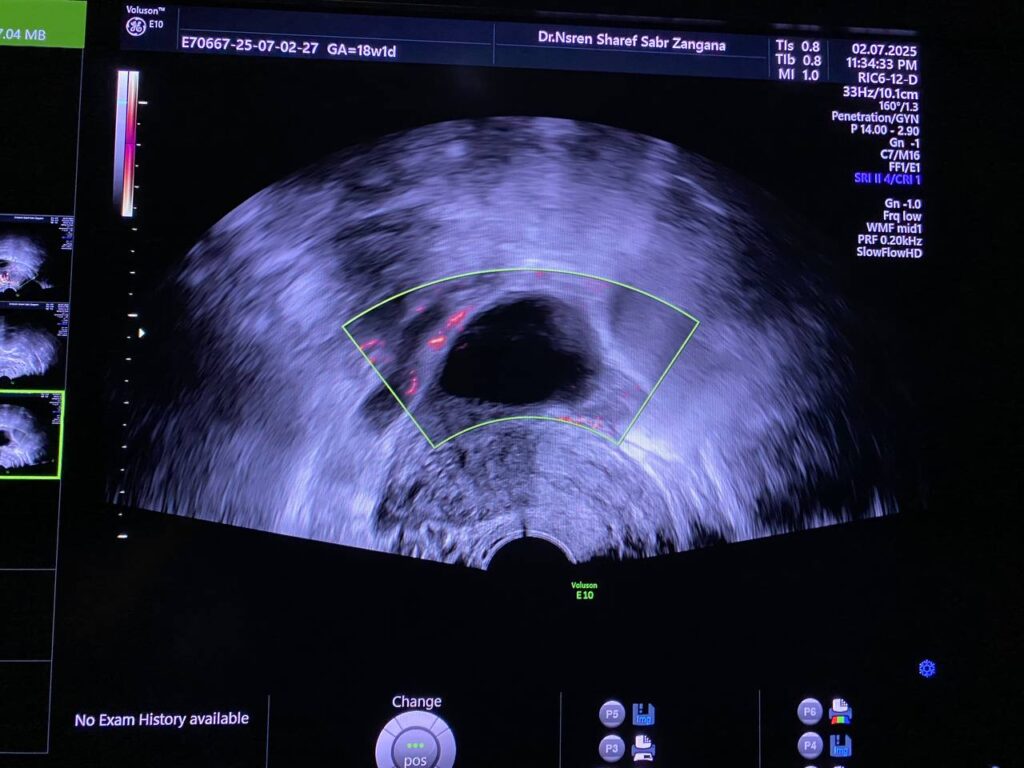

Bulky size, R/V uterus, endometrial lining thickness 13mm, with presence of isoechoic mass 36x12mm , within the cavity and nearly at level of interval os , incomplete abortion ? submucosal fibroid ? please for further study ill-defined endo-myometrial junctional zone, hypertrophy & asymmetry of the junctional myometrial layer, with presence few small cystic within the junctional layer, picture mostly of adenomyosis changes